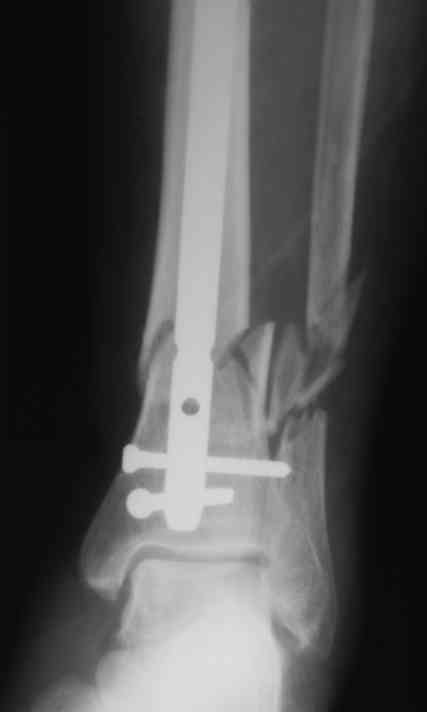

Уважаемые коллеги!БИОС занимаемся недавно. Хотелось бы услышать Ваше мнение па данному клиническому примеру. Пациенту 74 года.

Выполнен открытый БИОС, обнаружен выраженный остеопороз, один из проксимальных винтов(самый верхний) и один из дистальных (нижний) "сорвались". В средней трети - косо-поперечный перелом (на фото не захвачен) с хорошей репозицией. Клинически фиксация переломов стабильна. Выполнить МОС малоберцовой кости не представлялось возможным из-за фликтен по латеральной поверхности голени.

4. Диаметр стержня - 11, нержавейка, производитель Санатметалл

Открывали дистальный перелом - для качественной репозиции - у нас нет ЭОПа. Остеопороз у пациента - намного более выражен, чем у других пациентов-мужчин данной возрастной группы. По данным некоторых зарубежных авторов, при переломе обеих костей голени на одном уровне рекомендуется фиксация обоих. Руководитель нашей клиники настоятельно рекомендует фиксировать обе кости голени при повреждении на одном уровне. А в данном случае, учитывая выраженный остеопороз, у нас в отделении возникла дискуссия о необходимости дополнительной внешней иммобилизации у данного пациента для предупрежения прорезывания блокирующих винтов и вальгусного отклонения дистального отломка за счет силы латеральной группы мышц и отсутствия латеральной опоры на фоне выраженного остеопороза.